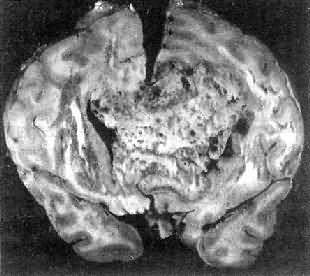

高度恶性的星形胶质细胞瘤称为多形性胶质母细胞瘤(glioblastoma multiforme),多见于成人。肿瘤好发于额叶、颞叶白质,浸润范围广,常可穿过胼胝体到对侧,呈蝴蝶状生长(图16-24)。瘤体因常有出血坏死而呈红褐色。镜下,细胞密集,异型性明显,可见怪异的单核或多核瘤巨细胞。出血坏死明显,是其区别于间变性星形胶质细胞瘤的特征。毛细血管明显增生,内皮细胞增生、肿大,可导致管腔闭塞和血栓形成。肿瘤发展迅速,预后极差,患者多在2年内死亡。

图16-24 多形性胶质母细胞瘤

在两半球内肿瘤呈蝴蝶状,边界不清,切面见有出血、坏死及液化